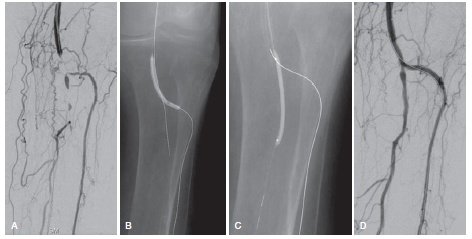

(3)腔内介入治疗,包括单纯球囊成行、支架成行、减容技术以及减容技术联合药物涂层球囊,由于其创伤小,恢复快等优势目前已经成为首选治疗方法。此外血管新生疗法等新型疗法也开始逐渐得到关注。

小腿动脉闭塞球囊扩张成型术后血流恢复通畅